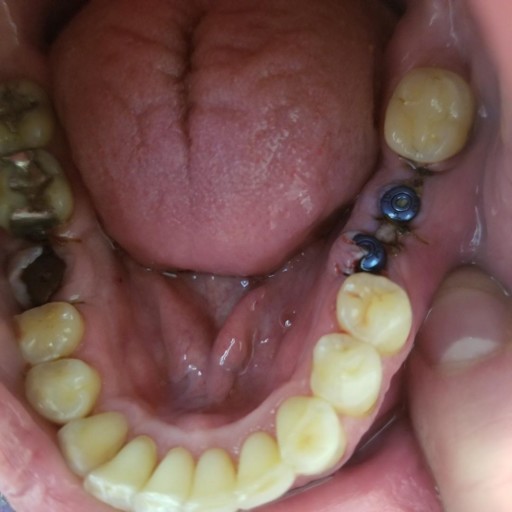

First I really love my DR BUT I am getting through the process of 2 front teeth dental implants. About 2 years ago I had a bone graph done on tooth # 8 with no issues. About 7 weeks ago I went in for the following: Tooth # 8 Surgical implant body : Endosteal All of the following on tooth # 9 Tooth # 9 Extracted Osseous graft by report Guided tissue regen-Resorb So 5 weeks after the process I went in and had the stitches removed. Two more weeks go by and on a Friday I start to have some irritation on my tooth next to where I had the Surgical implant body Endosteal. By Sunday it's getting bad and I can taste puss. I look with my dental mirror and next to number 7 is a white end of a suture that was obviously left behind. I figure no big deal and pull it out and about 2 inches on suture comes out. THEN after that I see a black head on my gum and touch it with a rubber dental pick and from that hole a "TI-Fixation Titanium implant Pin" just dropped right out onto the counter. It took me a hour on google images to figure out what it was. So I take it to see my DR 1st thing Monday morning and it worried me because I could see he was surprised. He put me on 500 mg 3X a day of Amoxicillin and Chlorhex Glu rinse solution. He then tells me we may have to take all of the previous work out and start over and it would be best to just replace it all! Now my insurance does not cover this stuff and I took a loan out on my 401K to pay for this. My question is to anyone who can help Is this normal? Did the pin and/or the suture cause this infection? My gut feeling by his reaction was something was missed during the procedure. I really like my doctor but if there is going to be more expense involved I don't think I should be charged if they did something wrong. I am not looking to sue him and I really like the man I just want a fair shake and my mouth fixed. Any opinions on the matter would be appreciated.

I had 3 implants done yesterday, with 2 that were next to each other (see picture). One is not aligned. I am also doing ortho care and went in today to have a new retainer fitted. The dentist said he did not want to do new impressions due to the...